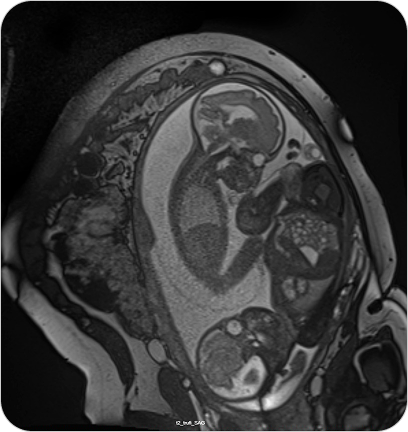

Resonancia Magnética Fetal

La resonancia fetal es un estudio no invasivo que permite observar con gran detalle el desarrollo del bebé en el útero. Es un complemento ideal de la ecografía cuando se necesita información más precisa.

La resonancia magnética fetal permite obtener imágenes detalladas del bebé durante el embarazo, sin utilizar radiación. Se utiliza como complemento del ultrasonido cuando se detectan hallazgos que requieren evaluación más precisa.

¿PARA QUE SE UTILIZA?

- Evaluar el desarrollo del sistema nervioso central fetal (cerebro y médula espinal).

- Detectar malformaciones cerebrales o anomalías estructurales.

- Valorar la anatomía de órganos internos en casos complejos.

- Confirmar o descartar hallazgos dudosos en ecografías.

- Planificar tratamientos o decisiones perinatales junto con el equipo obstétrico.

¿POR QUÉ ES UN ESTUDIO DESTACADO?

- No invasivo y seguro para la madre y el bebé.

- Alta definición de imágenes incluso en embarazos avanzados.

- Permite tomar decisiones médicas informadas y personalizadas.

- Evita resonancias post-natales.

Resonancia Magnética Fetal

La resonancia fetal es un estudio no invasivo que permite observar con gran detalle el desarrollo del bebé en el útero. Es un complemento ideal de la ecografía cuando se necesita información más precisa.

La resonancia magnética fetal permite obtener imágenes detalladas del bebé durante el embarazo, sin utilizar radiación. Se utiliza como complemento del ultrasonido cuando se detectan hallazgos que requieren evaluación más precisa.

¿PARA QUE SE UTILIZA?

- Evaluar el desarrollo del sistema nervioso central fetal (cerebro y médula espinal).

- Detectar malformaciones cerebrales o anomalías estructurales.

- Valorar la anatomía de órganos internos en casos complejos.

- Confirmar o descartar hallazgos dudosos en ecografías.

- Planificar tratamientos o decisiones perinatales junto con el equipo obstétrico.

¿POR QUÉ ES UN ESTUDIO DESTACADO?

- No invasivo y seguro para la madre y el bebé.

- Alta definición de imágenes incluso en embarazos avanzados.

- Permite tomar decisiones médicas informadas y personalizadas.

- Evita resonancias post-natales.